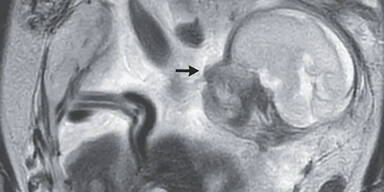

Viel schockierender für die Schwangere als auch die Ärzte war das Ergebnis der zweiten Untersuchung: Ihr Baby befand sich in ihrem Darm!

Ein außergewöhnliches Phänomen, das zwar nicht ganz neu, jedoch äußerst selten ist. Medizinisch spricht man von einer abdominalen Eileiterschwangerschaft. Dabei nistet sich eine befruchtete Eizelle außerhalb der Gebärmutter in der Bauchhöhle ein. Nur bei einem Prozent aller Eileiterschwangerschaften ist das der Fall.

Statt in der Gebärmutter hat sich die Eizelle in der Bauchhöhle eingenistet